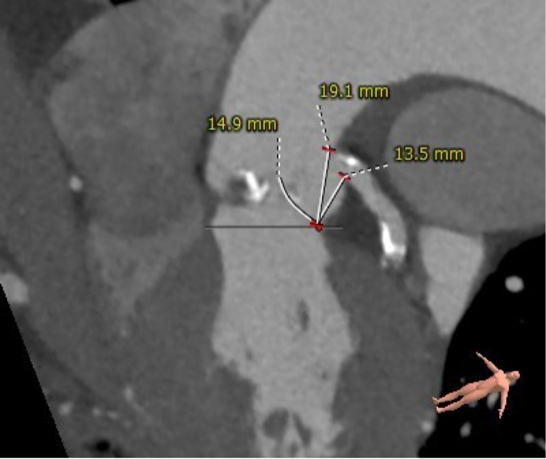

主动脉根部评估:

患者为79岁男性,术前超声心动图提示三叶式主动脉瓣重度狭窄伴中度关闭不全、瓣叶明显钙化增厚、峰值流速 3.63m/s、平均跨瓣压差 33mmHg、有效瓣口面积 0.9cm²;左心扩大,室间隔增厚;二尖瓣中轻度反流、三尖瓣轻度反流;LVEDd:59mm,LVEF:53%。